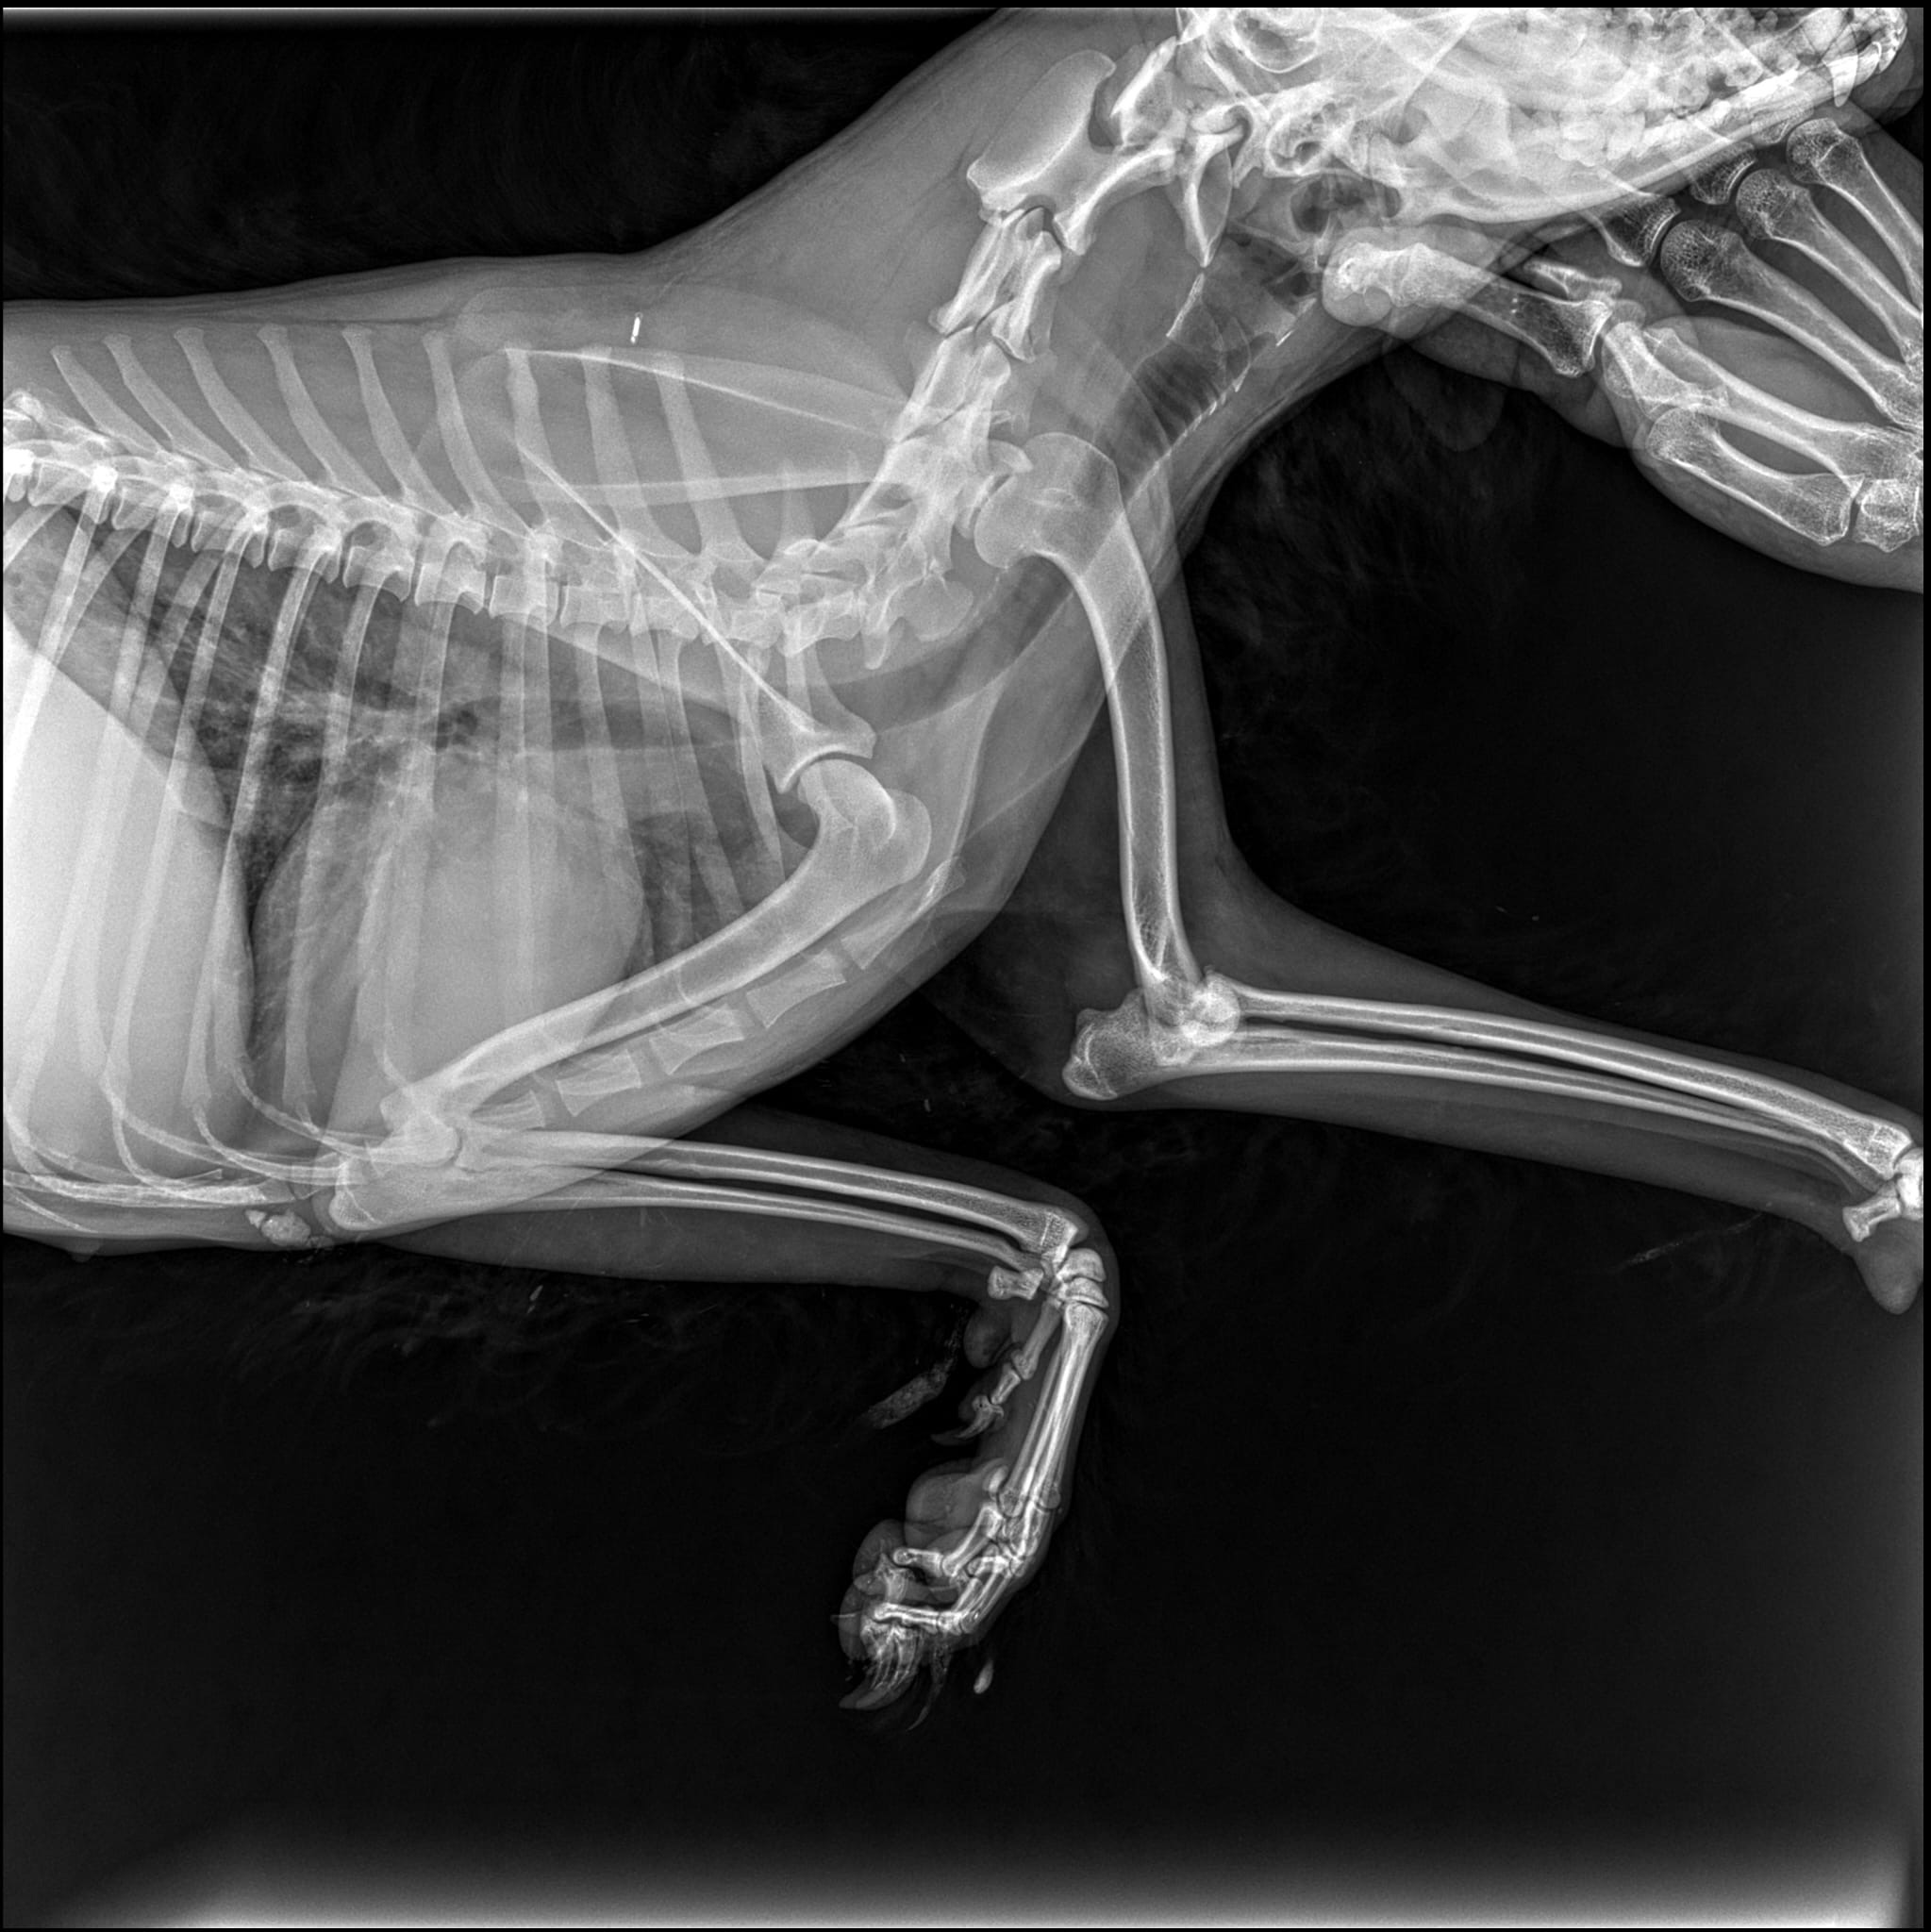

Wir haben Flöckchen nach Bukarest in eine Klinik gesandt, um zu schauen, ob man sie operieren kann. Sie wurde geröngt und man teilte uns mit, das man Flöckchen leider nicht operieren kann. Ihr Ellbogen ist verletzt. Sie hat laut Tierarzt eine Ellbogendysplasie und durch die Verletzung auch schon Arthrose.